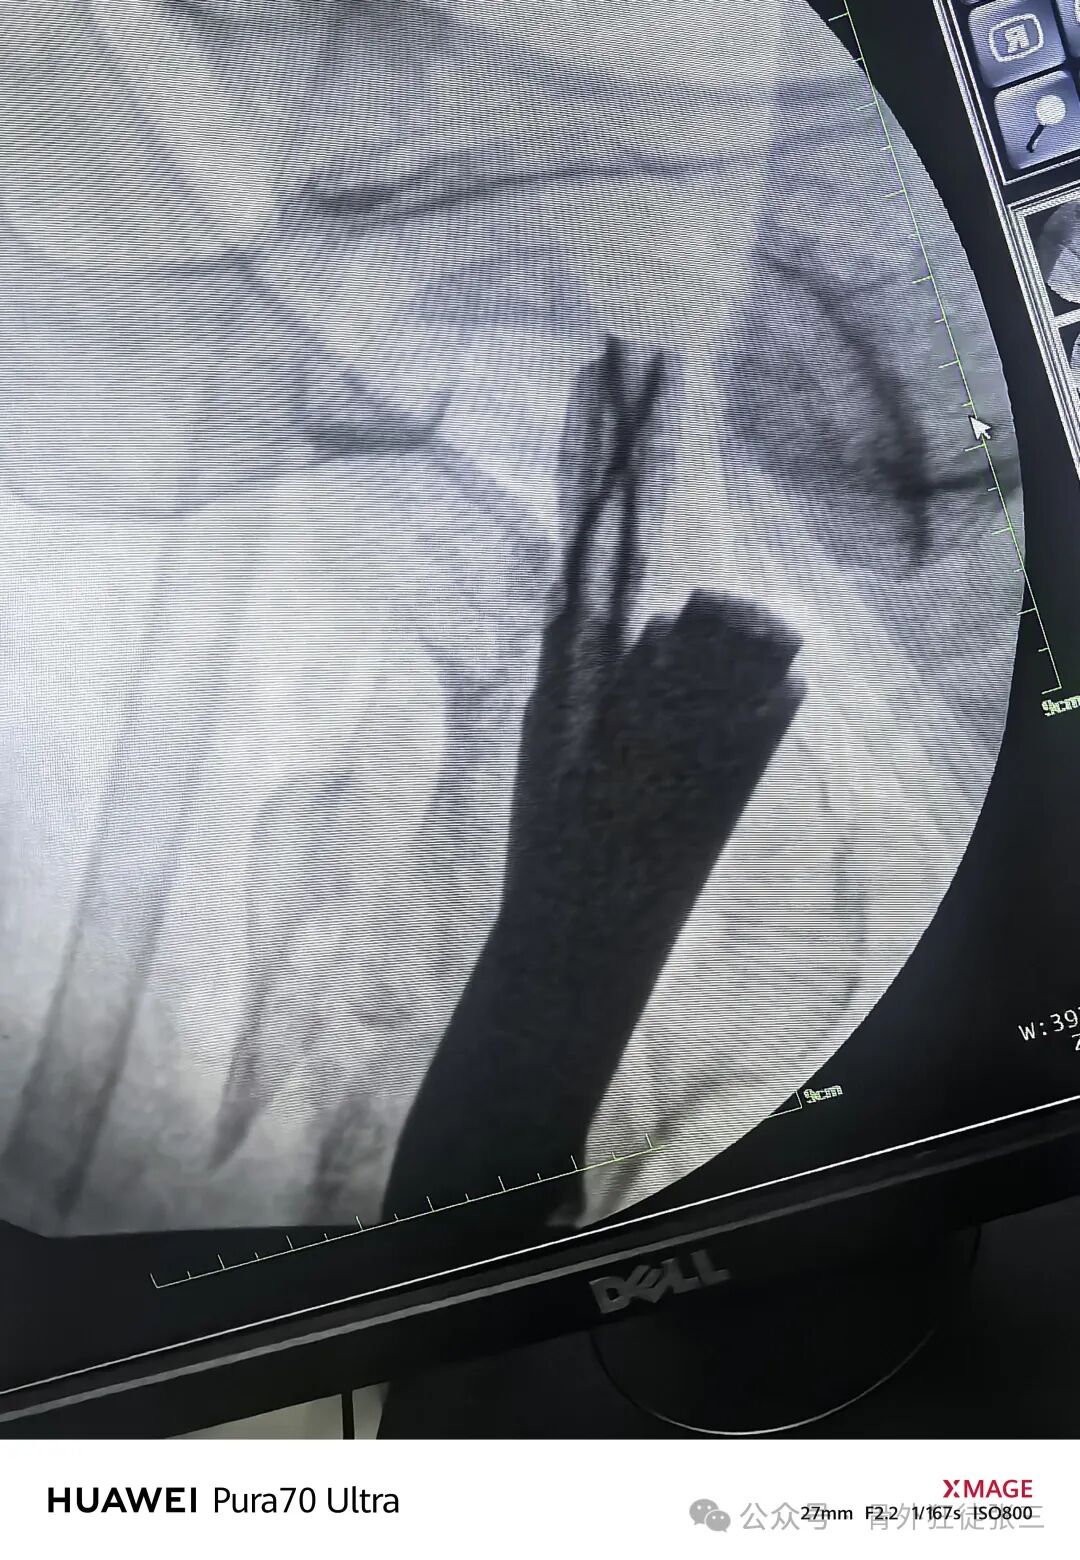

再次透视

正位复位满意

导针正位中下1/3

骨钩过牵了

有点阴性支撑

侧位导针居中